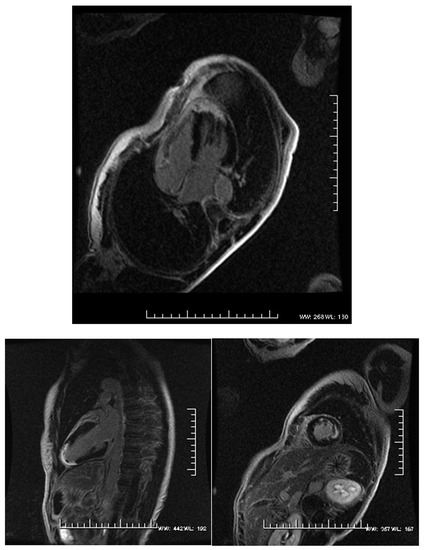

Can 3D RVEF be Prognostic for the Non-Ischemic Cardiomyopathy Patient but Not the Ischemic Cardiomyopathy Patient? A Cardiovascular MRI Study

:1. Introduction

2. Materials and Methods